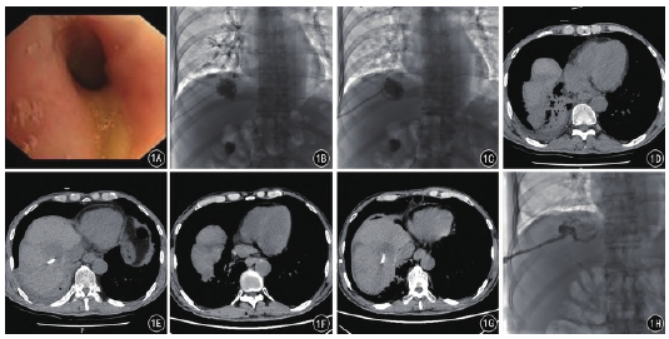

术后持续外引流2周,患者痰量明显减少,体温逐渐恢复至正常。7个月后造影复查可见脓腔消失,气管未显影,遂拔除引流管(图1)。

图1A~H A.支气管镜下可见右下叶支气管内黄色分泌物;B、C.PTCD造影可见胆管与支气管相通,置入外引流管引流脓液;D、E.术后复查CT平扫

可见右下肺大量积液,肝内可见一低密度灶;F、G.术后1个月CT可见右下肺积液明显减少,肝内病灶缩小;H.7个月后造影可见脓腔消失,气管未显影